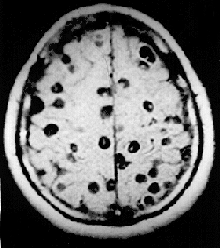

![]() Imagen por resonancia magnética de un paciente con neurocisticercosis que muestra múltiples cisticercos dentro del cerebro. | ||

Cuando la cisticercosis afecta al cerebro se llama neurocisticercosis. Se caracteriza por uno o múltiples quistes dentro del parénquima, y presenta un cuadro clínico con hidrocefalia, ictus epilépticos y signos neurológicos focales.